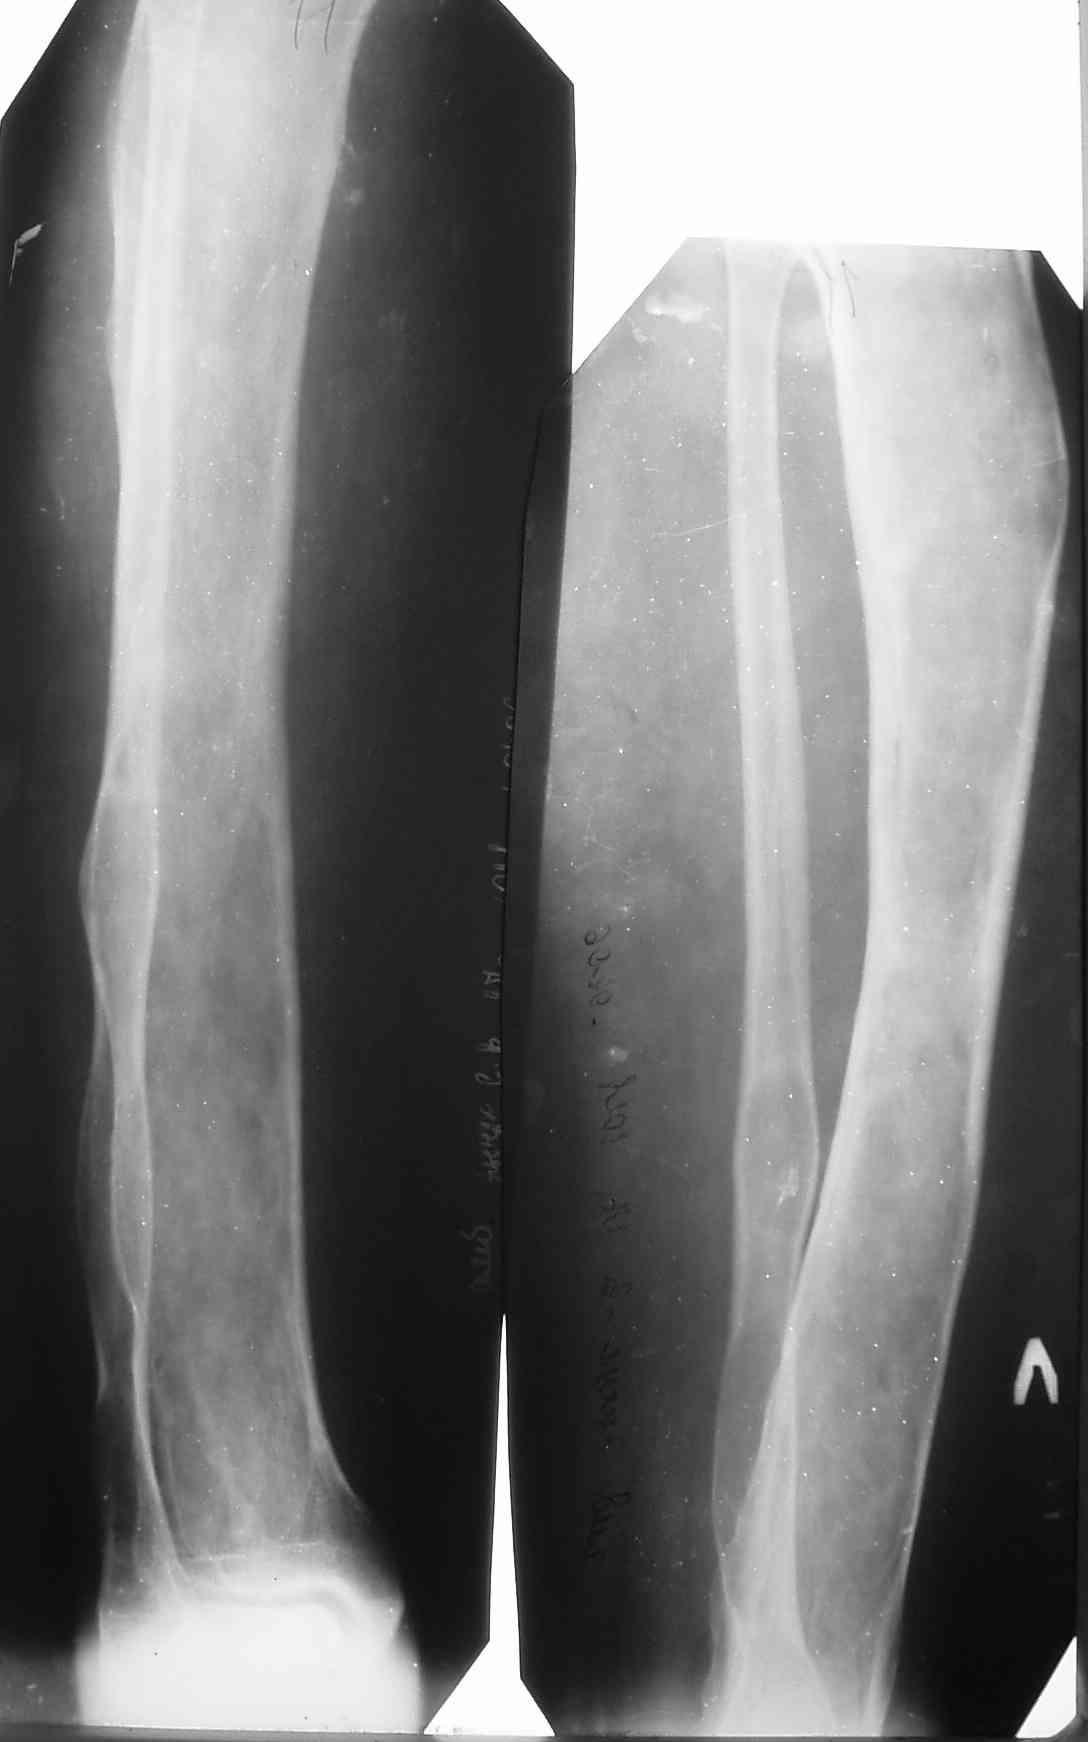

Я поддерживаю мнение доктора Odessky Jacob, что это образоавние возможно фиброзная дисплазия. Случай из моей практики - смотри рентгенснимки во вложении. Правда у моего пациента -полиосальная форма и болезнь проявилась в раннем детстве.